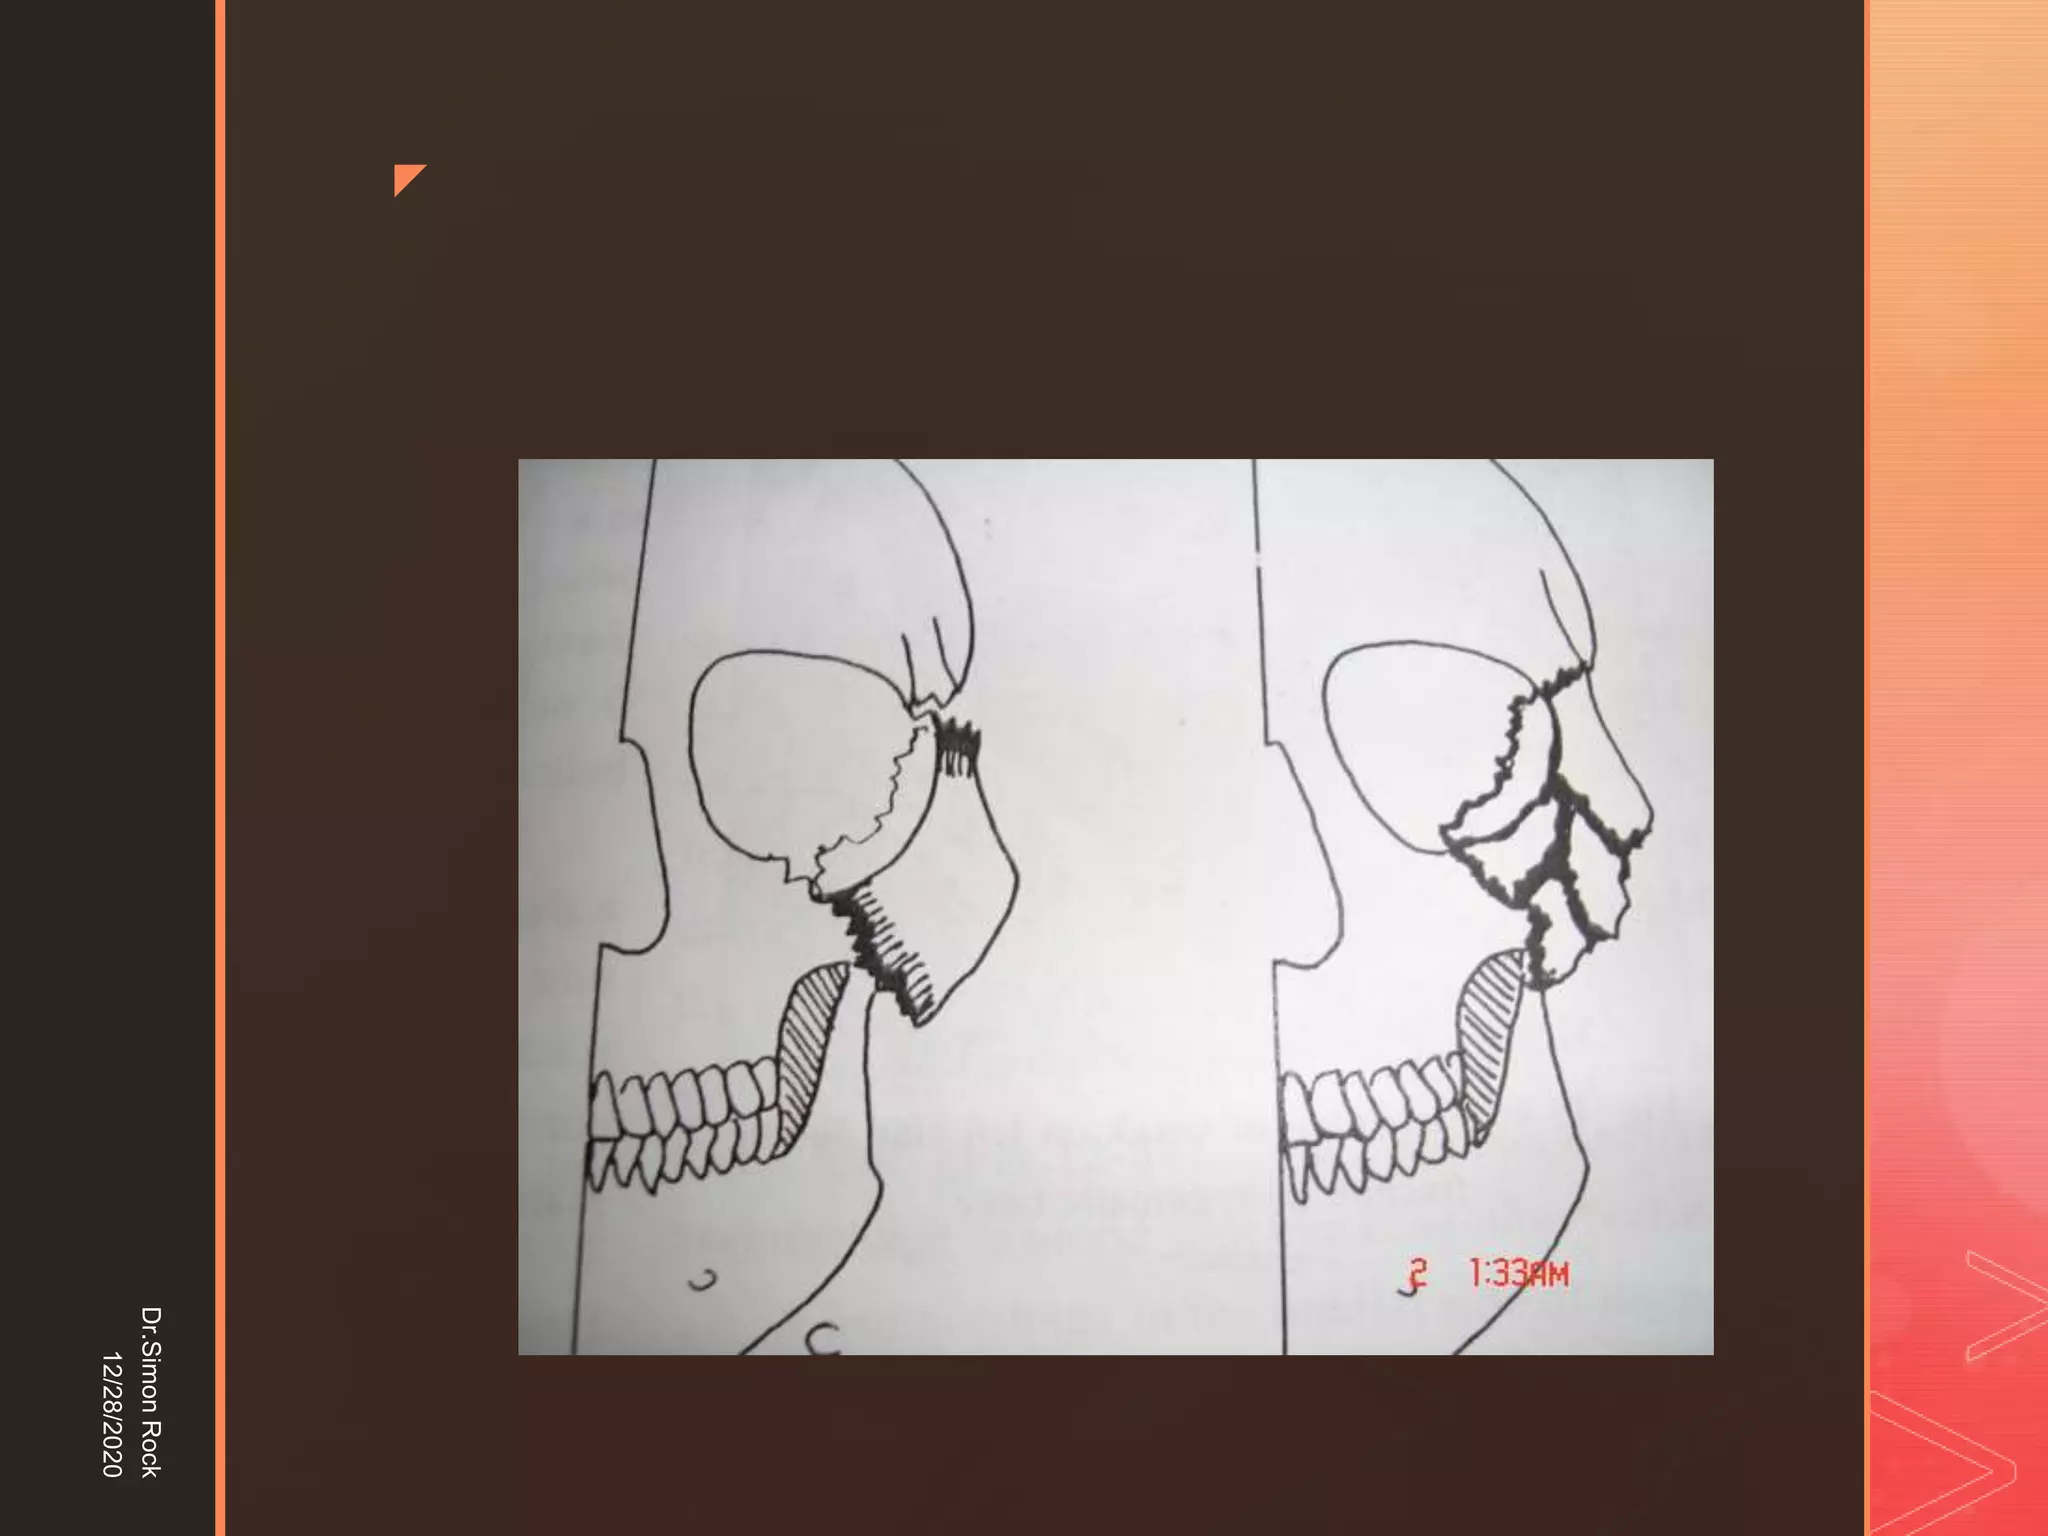

This document discusses the anatomy and fractures of the zygomatic bone. It notes that the zygoma forms the cheekbone and articulates with several other facial bones. Zygomatic fractures most commonly occur in the arch or body due to blunt trauma. Diagnosis involves checking for diplopia, ecchymosis, and other signs of orbital or facial bone involvement. Treatment may involve closed or open reduction based on the severity of displacement. Closed reduction techniques try to elevate the bone back into position without surgery, while open reduction requires surgical exposure and fixation of the fracture site.